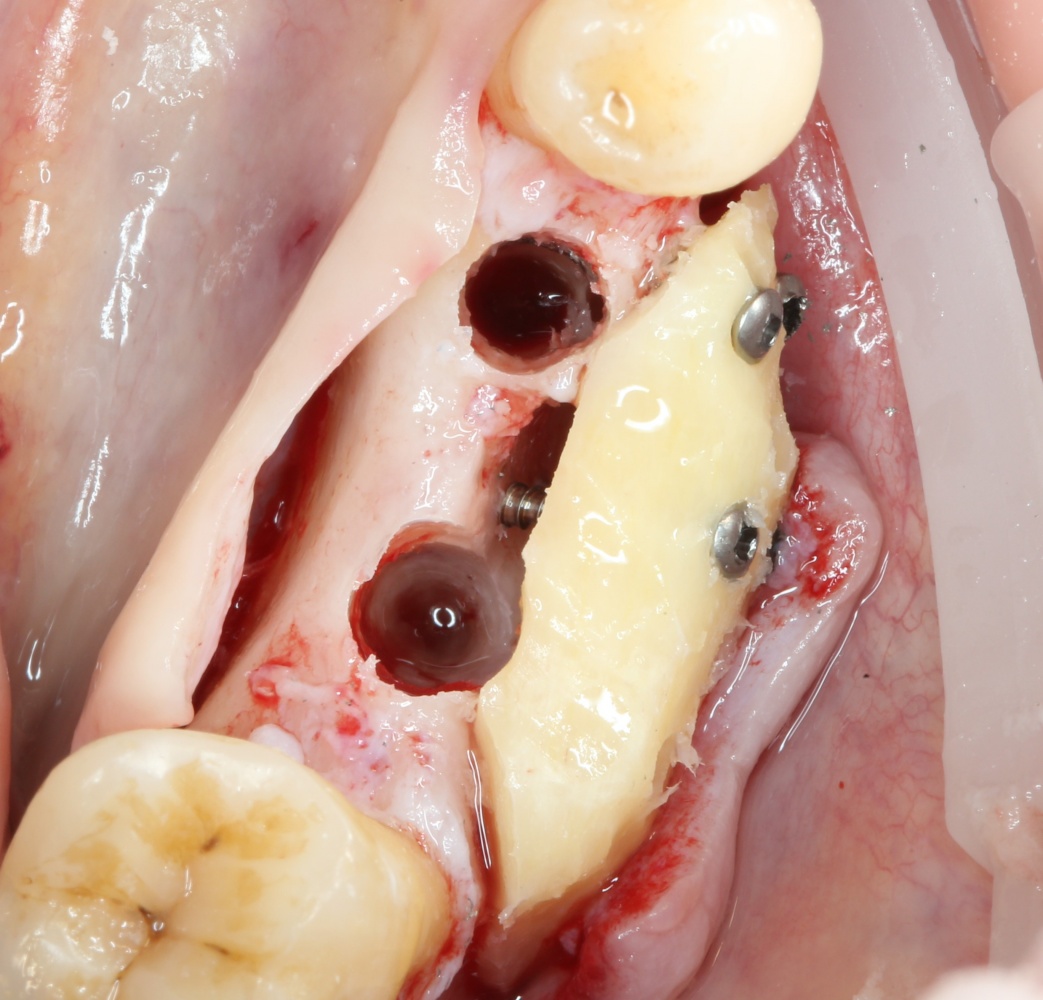

Скелетирование альвеолярного гребня. В том числе, участка для забора аутокостного трансплантата:

A09A5445 (2) A09A5446 (2)

Следующим этапом происходит формирование и забор аутокостного фрагмента для пересадки:

A09A5447 (2) A09A5448 (2)

Далее, примеряем и адаптируем костный блок:

A09A5449 (2) A09A5450 (2)

Готовим его к фиксации:

A09A5451 (2)

Многие ошибочно предполагают, что большое количество дырок в блоке нужно для того, чтобы «всё лучше срослось». На деле, большое количество отверстий в аутокостном фрагменте даст нам возможность переставлять вины и адаптировать его «на месте». А это особенно важно для одномоментной установки имплантов, потому что винты не должны попасть в проекцию будущей лунки.

Фиксация костного блока:

A09A5452 (2) A09A5453 (2)

Для этого стоит использовать длинные винты. В противном случае, при подготовке лунки под имплантат костный блок может отлететь.

Переставляя винты и пришлифовывая аутокостный фрагмент, можно добиться более-менее точного соответствия принимающему ложу:

A09A5457 (2) A09A5458 (2)

Теперь можно готовить лунки под импланты:

A09A5459 (2)

В данном случае я планирую установить импланты Nobel Replace Conical Connection:

A09A5461 (2) A09A5462 (2)

Операция почти закончена. Обратите внимание, на два момента:

1. Блок явно больше, чем нужно. Это связано с тем, что в процессе интеграции происходит атрофия графтов (причем, абсолютно любых), и мы должны закладывать этот уровень атрофии при планировании объемов костной пластики. В среднем, плюс 30% к тому, что нам нужно.

2. Между блоком и принимающим ложем есть пустое пространство. Поэтому область операции необходимо изолировать барьерной мембраной от быстро растущих мягких тканей. Я использую Geistlich BioGide 25×25 mm:

A09A5466 (2) A09A5467 (2)